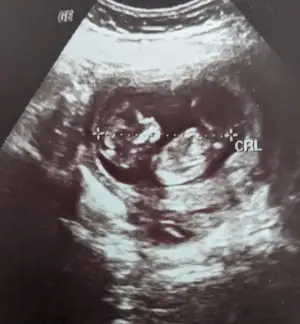

Ay kızlar benimkinin cinsiyetini de yorumlar mısınız 🥰🥰

Eklentiler

• PXL_20230907_131247115~2.webp

PXL_20230907_131247115~2.webp

37,2 KB · Görüntüleme: 95